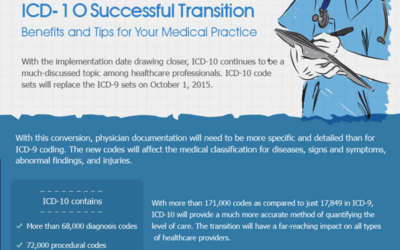

ICD-10 Successful Transition – Benefits and Tips for Your Medical Practice